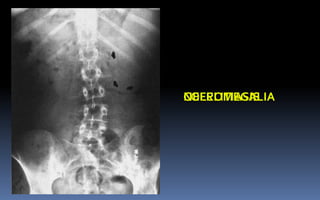

PROYECCION SIMPLE DE ABDOMEN

CRITERIOS DE EVALUACION P.S.A.

 Apreciar desde el abdomen

superior hasta la sínfisis del

pubis.

 Lumbares, pelvis y ultimas

costillas sin rotación.

 Apófisis espinosas en el

centro de cuerpos

vertebrales.

 Ver el bazo, riñones, psoas

y “borde inferior hepático

INTERPRETACION

 Estructuras óseas

(densidades).

 Tejidos blandos.

 Psoas.

 Bazo.

 Niveles Hidroareos.

 Intestino delgado.

 Colon.

 Silueta Renal.

PATRON AEREO DEL INTESTINO